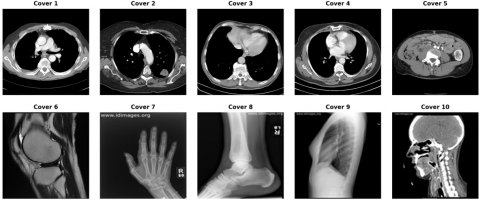

The experimental evaluation employed two comprehensive datasets to ensure thorough validation of the DSSSF. The primary dataset consisted of medical images obtained from the DICOM Library, similar to the study by Elhadad et al. [12], comprising high-resolution grayscale medical images with dimensions of 512 × 512 pixels. These images included various medical imaging modalities such as X-rays, CT scans, and MRI images, as illustrated in Figure 4. It has diverse textural characteristics essential for comprehensive steganographic evaluation. The secondary validation dataset incorporated images from the CT Medical Images database (https://www.kaggle.com/datasets/kmader/siim-medical-images), offering additional medical image samples with varying complexity levels and anatomical structures. To maintain consistency in image labeling, all images are uniformly labeled from Cover 1 to Cover 10, as presented in Table 2.

Figure 4. Sample cover images dataset taken from DICOM Library

Note: available at https://www.dicomlibrary.com/.

Table 2. Datasets filename

Image Name

File Name

Cover 1

ID_0001_AGE_0069_CONTRAST_1_CT

Cover 2

ID_0002_AGE_0074_CONTRAST_1_CT

Cover 3

ID_0003_AGE_0075_CONTRAST_1_CT

Cover 4

ID_0004_AGE_0056_CONTRAST_1_CT

Cover 5

ID_0005_AGE_0005_CONTRAST_1_CT

Cover 6

ID_0006_AGE_0010_CONTRAST_1_CT

Cover 7

Hand

Cover 8

Leg

Cover 9

Chest

Cover 10

Head